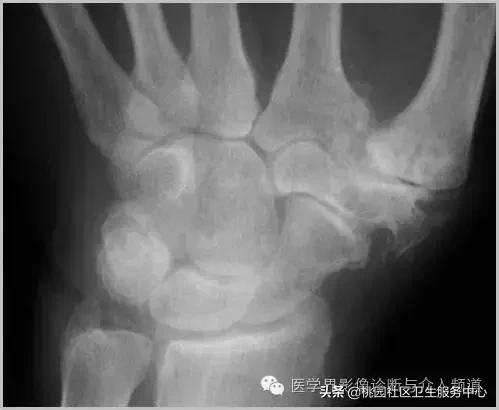

一、肿瘤样钙质沉着症

累及多个关节,范围较大,表现为多房囊状的高密度影。

肿瘤样钙质沉着症